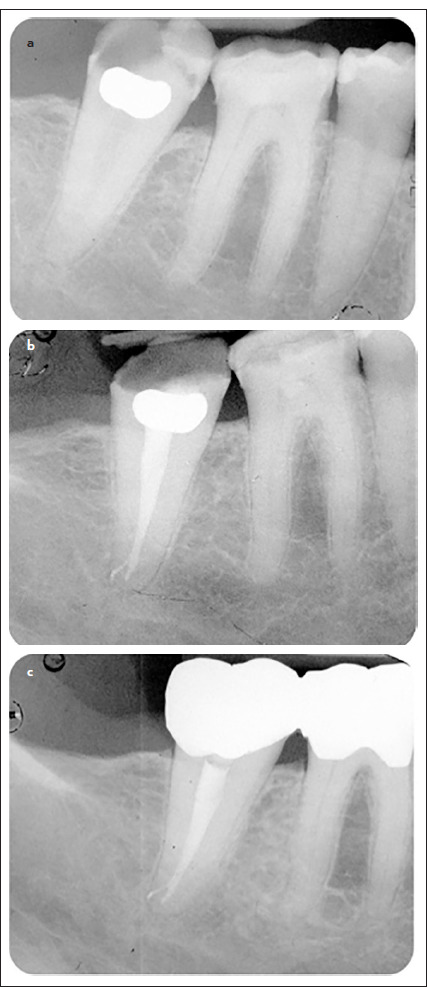

Methods: Healthy patients were consecutively treated by a cohort of postgraduate operators. Root canal filling procedures were performed with NiTi rotary instrumentation, while non-surgical retreatments were performed using NiTi reciprocating instruments. Root canal filling procedures were performed using Ceraseal and the single cone technique. Post-endodontic restorations were performed after 15 days. Provisional and definitive crowns were positioned in case of non-sufficient coronal structure. Periapical radiographs were made before treatment, after filling, and at each follow-up visit (6, 12, 24 and 36 months). The periapical Index (PAI) was used to assess the presence of periapical lesions and their modifications over time. Success (absence of periapical radiolucency, PAI <3) and survival rates were evaluated. The presence of apical extrusion was also radiographically assessed. Linear regression analysis was used to investigate changes in mean PAI scores, and logistic regression analysis was used to investigate changes in the percentage of healed cases. All analyses were replicated using two distinct approaches: per protocol (PP) (treatments who completed the follow-up) and intention to treat (ITT) (all root canal treatments). A significance level of 5% was used for all statistical tests (α=0.05).

Results: Fifty-eight endodontic treatments in 52 patients were performed (ITT). Thirty-eight endodontic treatments in 33 patients completed the 3 years of follow-up with a survival rate of 92.7%. The success rate was 85.4% (PP).

Conclusion: The use of Ceraseal associated with the single cone technique was safe in maintaining endodontically affected teeth. (EEJ-2024-01-02).